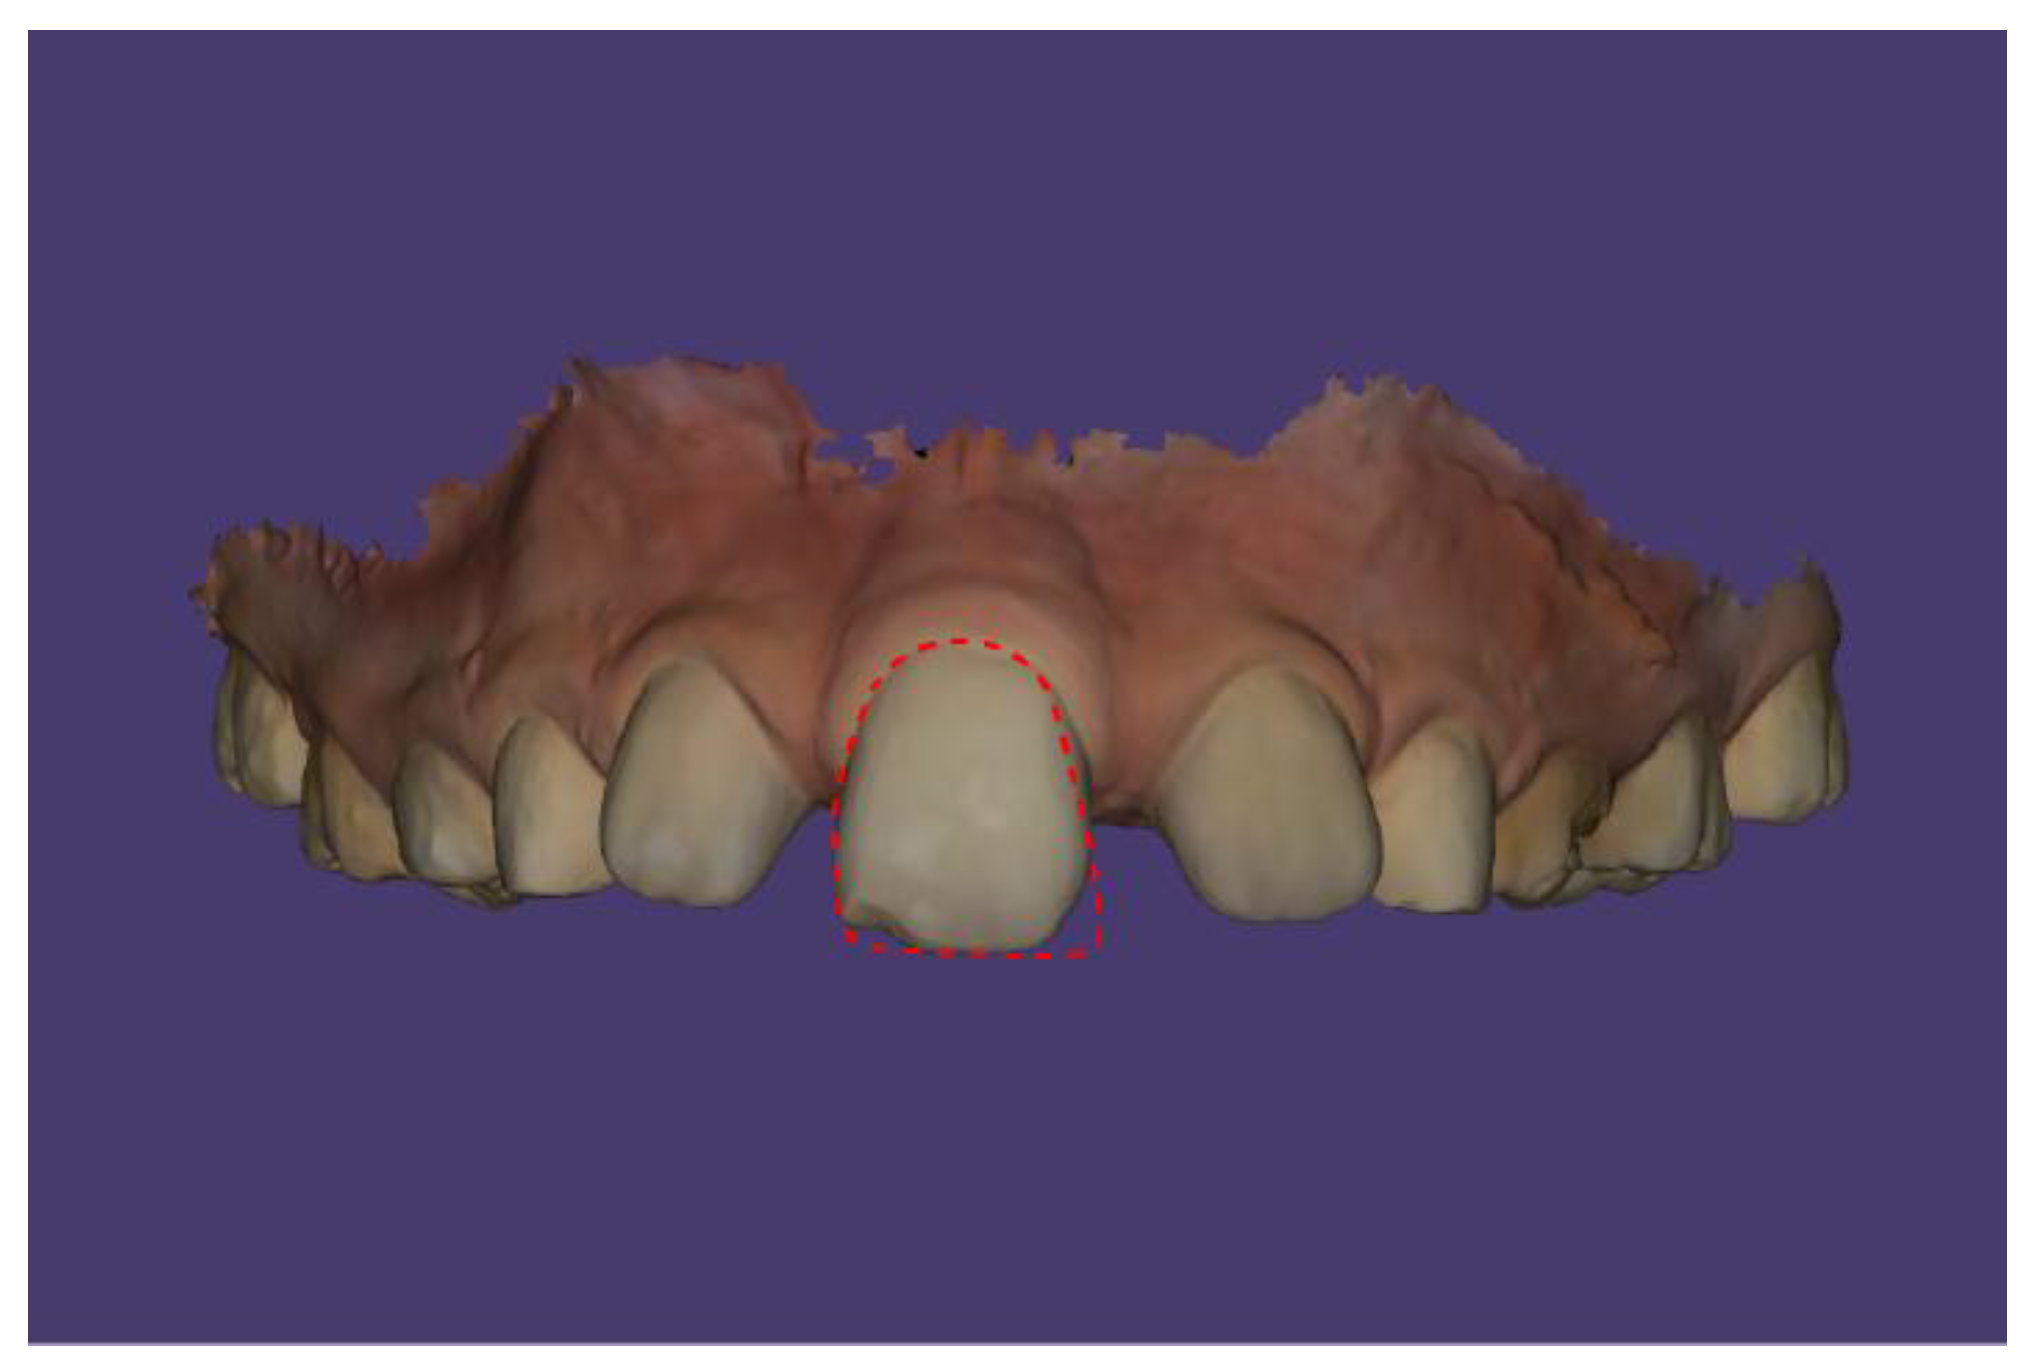

Case Description